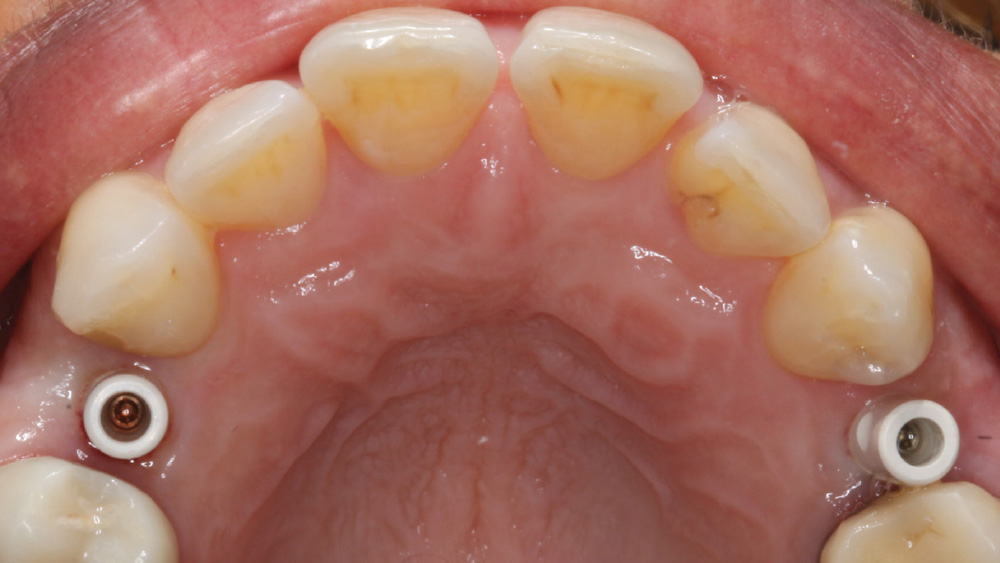

CASE REPORT

The following case, which I performed alongside Dr. Stephanie Tilley of Pensacola, Florida, illustrates the use of both surgical techniques for the same patient, who presented with edentulous spaces in the areas of both right and left maxillary first bicuspids. Due to varying soft-tissue volume on each side of the arch, implant surgery was performed using a flapless procedure for one site, while the attached gingiva was reflected to expose the available hard tissue for the other. As a result of proper site evaluation, treatment planning and restorative-driven implant placement, both surgical techniques led to successful outcomes for the patient.